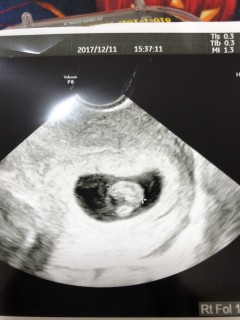

写真:7w1d:もとさん

7週1日のエコー写真です。去年妊娠した時は出血が続いてて、赤ちゃんの成長が遅くて流産するかもって言われて、8週になってすぐ赤ちゃんが出てきてしまい流産でした。すごく悲しかった。でもまた妊娠することができて赤ちゃんが戻ってきてくれたのかと嬉しかったです。今回不安でした。でも9、1㎜に成長してくれてホッとしました。来週母子手帳もらえる。すごくうれしいです(^-^)